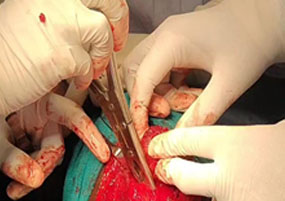

42/M Patient came with H/o self inflicted, cut throat Diagnosed -Self inflicted cut injury /zone-1 and 2 neck injury . Presented with severe bleeding, hypovolumic shock .Airway secured and fluids started . Pt was shifted to emergency OT and resuscitation started and stabilized by our anesthesia team. Patient underwent Emergency exploration of neck and bleeding IJV was ligated and ryles tube inserted .There were two penetrating wounds in neck , one in zone 1 which was exposed and Tracheostomy done. In zone 2, there was complete transection of thyroid cartilage and epiglottis, completely separated and tear went upto pyriform mucosa. Cartilage repair and mucosa repair done . It is first of its kind , cut throat injury with vessel bleed and pt revived in almost arrested stage and successfully surgical repair done .